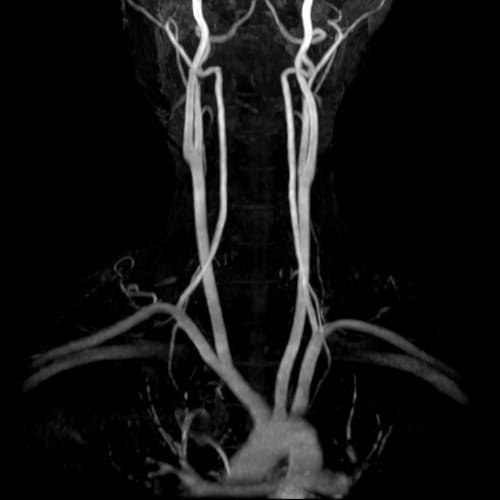

頸動脈MRA(血管撮影)

脳MRI

首の血管(頸動脈)を撮影し3次元的に観察することで、動脈硬化や狭窄の有無を調べます。

脳へ繋がる重要な血管であり、脳梗塞の予防において重要なポイントです。